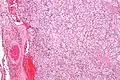

| Micrograph of a carotid body tumour (a type of paraganglioma). | |

On microscopic inspection, the tumor cells are readily recognized. Individual tumor cells are polygonal to oval and are arranged in distinctive cell balls, called Zellballen.[10] These cell balls are separated by fibrovascular stroma and surrounded by sustentacular cells.

By light microscopy, the differential diagnosis includes related neuroendocrine tumors, such as carcinoid tumor, neuroendocrine carcinoma, and medullary carcinoma of the thyroid.

With immunohistochemistry, the chief cells located in the cell balls are positive for chromogranin, synaptophysin, neuron specific enolase, serotonin, neurofilament and Neural cell adhesion molecule; they are S-100 protein negative. The sustentacular cells are S-100 positive and focally positive for glial fibrillary acidic protein. By histochemistry, the paraganglioma cells are argyrophilic, periodic acid Schiff negative, mucicarmine negative, and argentaffin negative.

Micrograph of a carotid body tumor